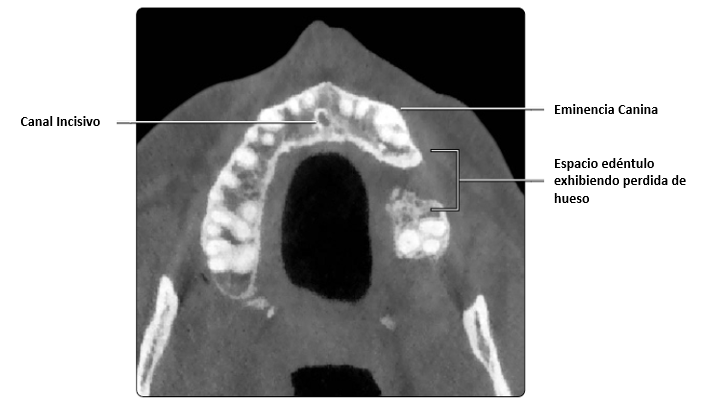

Vista axial de maxilar superior. Se muestra el canal incisivo que puede presentarse como único (como se muestra en la imagen) o en pareja. Puede ser centrado o ligeramente lateral a la línea media (como se muestra en la imagen).